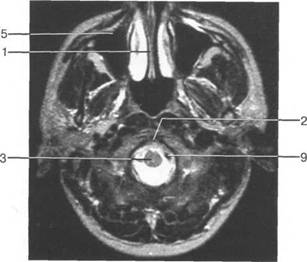

Задняя череп 13513u2010n 85;ая ямка представляет собой часть основания череп 13513u2010n 72;, ограниченную централь

Следует отметить, что в настоящее время оптимальным методом исследования структур задней череп 13513u2010n 85;ой ямки является МРТ, которая, в отличие от КТ, лишена артефактов от кост

Мозжечок заполняет практически весь объем задней череп 13513u2010n 85;ой ямки. Его поперечный раз

IV IV IV IV III IV

височная доля; 17 - полушарие мозжечка; 18 - |

Следует остановиться на анатомии подпаутинных пространств задней череп 13513u2010n 85;ой ямки IV 20 мм. Между основанием череп 13513u2010n 72; и нижней поверхностью мозга от большого затылочного отверстия вдоль ската и спинки турецкого седла простирается задняя базальная цистерна. В зави IV